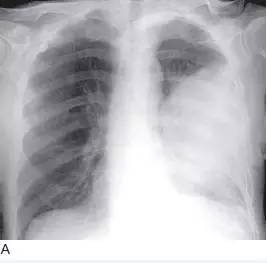

图13 大细胞肺癌

A. 胸片显示左肺巨大肿块;B. 在对比增强CT 上,巨大肿块占据左肺,左侧胸腔可见积液